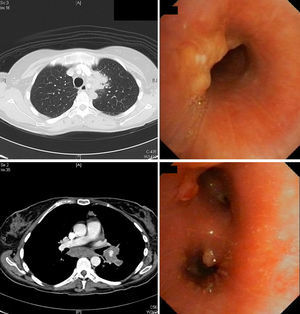

Una mujer de 45años residente en India hasta hacía 8meses consultó por un cuadro de 3meses de evolución de fiebre diaria hasta 38°C, anorexia, pérdida de peso, tos seca y disnea, sin mejoría tras 7días de tratamiento con amoxicilina-clavulánico. A la exploración tenía buen estado general; solo destacaban 2nódulos subcutáneos de 1cm en el hipocondrio izquierdo, móviles, de consistencia gomosa, algo dolorosos y sin signos inflamatorios, con otro similar en la mano izquierda. En la analítica se detectó anemia, leucocitosis y trombocitosis. La radiografía de tórax mostró una masa en el mediastino anterior, que en la tomografía axial computarizada (TAC) se informó como «masa en lóbulo superior izquierdo y región hiliar ipsilateral, con infiltración de mediastino anterior, que estenosa la luz bronquial; adenopatías subcarinales y paratraqueales ipsilaterales, junto con múltiples nódulos independientes en pulmón izquierdo, implantes pleurales y nódulos subcutáneos abdominales». En la broncoscopia la mucosa estaba inflamada, con implantes de aspecto tumoral y estenosis bronquial izquierda. En las biopsias se descartó malignidad, pero tanto en las bronquiales como en la de uno de los nódulos abdominales se observaron granulomas no necrosantes. Con cultivos inicialmente negativos, creció después un Mycobacterium tuberculosis multisensible en esputo, por lo que se diagnosticó de TBC diseminada con afectación endobronquial de tipo tumoral y cutánea. La paciente mejoró rápidamente con tuberculostáticos y corticoides. La broncoscopia fue normal a los 6meses, mientras que la TAC solo mostraba engrosamiento residual de partes blandas (fig. 1).

Chung y Lee3 la clasifican en 7 subtipos: caseificante (12-43%), edematoso-hiperémica (14-44%), fibroestenótica (6-10,5%), tumoral (10,5-30%)3–5, granular, ulcerativa y tipo bronquitis inespecífica; las 4 primeras con peor pronóstico, pues asocian estenosis bronquial3. Parecen representar diferentes estadios de la misma enfermedad, comenzando con lesiones inflamatorias y granulomas submucosos que evolucionan a masas, fibrosis y estenosis de la vía aérea4,5. El subtipo tumoral tiene masas endobronquiales, superficie hemorrágica y cubierta necrótica, simulando un carcinoma epidermoide. Son factores de riesgo para la estenosis bronquial residual: edad superior a 45años, tipo fibroestenótico y diagnóstico tardío2,5; su tratamiento incluye dilatación endoscópica, resección mecánica o endoprótesis, además de los corticoides, que parecen efectivos en las fases iniciales y en las formas caseificante/tumoral4, motivo por el cual fueron utilizadas en nuestra paciente, en quien se consiguió la resolución ad integrum.